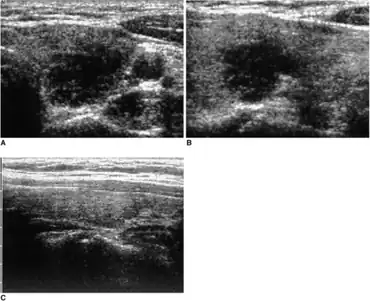

De Quervain's thyroiditis, also known as subacute granulomatous thyroiditis or giant cell thyroiditis, is a member of the group of thyroiditis conditions known as resolving thyroiditis. People of all ages and genders may be affected.

Signs and symptoms

Patients will experience a hyperthyroid period as the cellular lining of colloid spaces fails, allowing abundant colloid into the circulation, with neck pain and fever. Patients typically then become hypothyroid as the pituitary reduces TSH production and the inappropriately released colloid is depleted before resolving to euthyroid. The symptoms are those of hyperthyroidism and hypothyroidism. In addition, patients may suffer from painful dysphagia. There are multi-nucleated giant cells on histology. Thyroid antibodies can be present in some cases. The clinical presentation during the hyperthyroid phase can mimic those of Diffuse Toxic Goiter or Graves' disease. In such cases, a radionuclide thyroid uptake and scan can be helpful, since subacute thyroiditis will result in decreased isotope uptake, while Graves' disease will generally result in increased uptake. Distinguishing between these two types of disease is important, since Graves' disease and Diffuse Toxic Goiter can be treated with radioiodine therapy, but subacute thyroiditis is usually self-limited and is not treated with radioiodine.

In the initial phase of damage to the gland, preformed thyroid hormone will 'fall out' of the damaged cells. This leads to symptoms and biochemistry of an overactive thyroid (feels hot, trembly, anxious, loses weight, fast heart rate, sweaty, greasy hair), with raised free T3 and free T4, and a suppressed thyroid stimulating hormone (TSH) value. The damaged cells will no longer be able to take up iodine in order to manufacture further supplies of thyroid hormone, and thus in due course the patient comes to experience the symptoms of an underactive thyroid (feels cold, tired, depressed, gains weight, dry skin and hair) with low free T3 and free T4, and eventually increased TSH.

Diagnosis

With the standard overactive thyroid, iodine uptake into the thyroid is avid, whereas if the cells are damaged, then uptake is poor. In this way, if there is doubt about whether the patient has too much thyroid hormone because of de Quervain's thyroiditis, then measuring radio-iodine uptake or technetium uptake gives a clear cut answer as it will be higher than normal in standard thyrotoxicosis and lower than normal in de Quervain's.